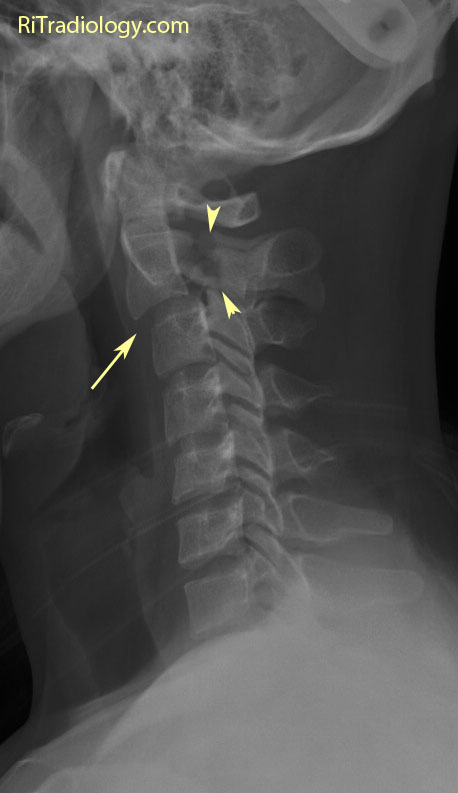

Hangmans Fracture

Hangman's fracture - Wikipedia Hangman's Fracture - Physiopedia Hangman's Fracture, C2 Fracture - Everything You Need To Know - Dr. Nabil Ebraheim - YouTube Hangman fracture | Radiology Reference Article | Radiopaedia.org | Hangmans Fracture